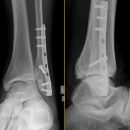

Sprunggelenk

Weber A

Es wurden keine Bilder gefunden.

Weber B

Weber C + dorsales Volkmann

Trimalleoläre

Vorderes Volkmann + lat. Talusschulter